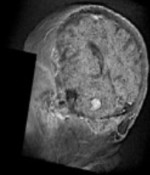

A comprehensive dataset of annotated brain metastasis MR images with clinical and radiomic data

Growth dynamics of brain metastases differentiate radiation necrosis from recurrence

Neurooncology Advances 5(1), vdac179 (2023)

Growth exponents reflect evolutionary processes and treatment response in brain metastases

npj Systems Biology and Applications 9, 35 (2023)